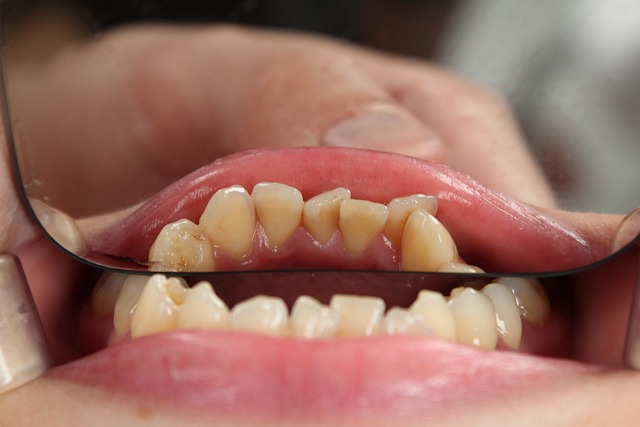

✔ 옆으로 누운 사랑니: 앞 치아를 밀어 치열이 틀어지고 통증 발생

❗ 사랑니가 곧고 정상적으로 자리 잡았다면, 특별한 문제가 없는 한 발치하지 않아도 됩니다.